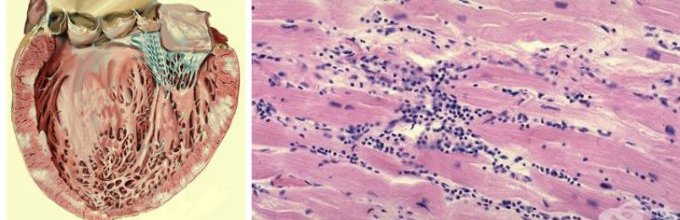

Межуточный миокардит: гистологические исследования

Раздел: Идеи и советы